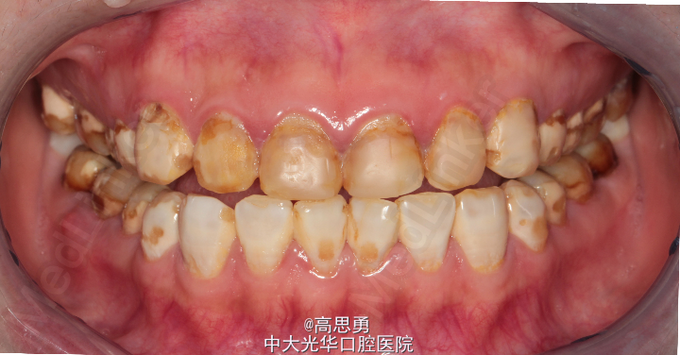

主诉:全口氟斑牙,要求美容修复。 现病史:患者出生并长期生活于广东省朝阳市,自恒牙萌出以来,全口牙表面上有白色、褐色斑块,未做特殊处理,现因自觉严重影响美观,遂到我院修复科要求治疗。 既往史:无心血管病、血液病、无传染病史、无药物过敏史。

检查(包括专科检查及辅助检查):详细记录口腔颌面部检查、牙体检查及牙周检查(附修复前照片,影像学检查图片) 1、全身状况良好,无全身系统性疾病,自主行动能力正常。精神心理状态无异常。 2、颌面部左右对称,面部比例协调,面部正面形态尖圆形。颞下颌关节运动无异常,开口型无异常,颞下颌关节无弹性,无压痛。 3、口内黏膜未见瘢痕,舌运动无异常。唇颊系带附着无异常,唾液分泌无异常。 全口牙表面广泛着色,可见白垩色到茶褐色的斑块,牙体完整,未见明显的实质缺损。牙龈正常,无肿胀无瘘管。

诊断:氟斑牙(着色型、中度) 患者意愿:患者希望尽快解决全口牙颜色改变的问题,不希望接受效果不明确、复诊次数多、维持时间短的治疗方案,可以接受费用较高的治疗方案,希望达到牙齿永久的形态、排列、颜色的尽可能完美的效果,但要求尽量少损伤牙体结构。下颌牙暂时不修复。 治疗方案:全瓷贴面修复,改善前牙美观。